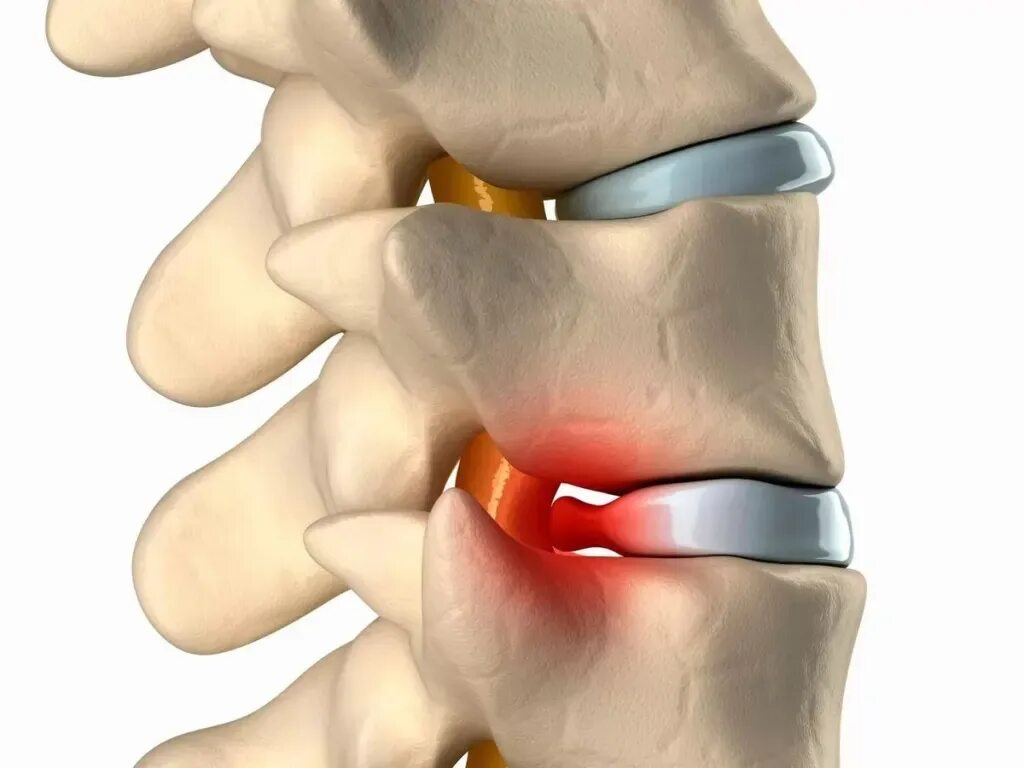

Лечение протрузии диска l5